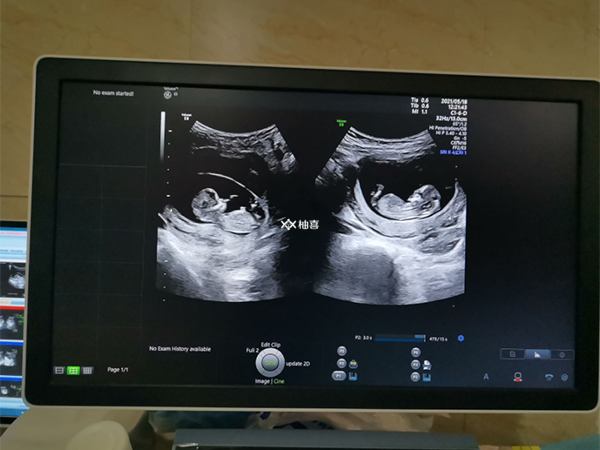

对于做试管婴儿手术的姐妹而言,绝大部分是比较想要生双胞胎的,而且对于其成功率以及费用是比较关心的。但其实,大家更应该关心的是其带来的生育风险,如孕期并发症(高血压、贫血、羊水过多、胎盘早剥)、分娩时的各种风险(大出血、产后出血或感染)、胎儿风险(早产儿、生长受限、胎儿畸形、双胎输血综合征)等等。

随着三胎的开放,因其各种原因,我国适龄人群中不孕不育患者人数高达4000万,约占育龄人口的12.5%,也就是说每八个人就有一个人是不孕不育患者。通常来说,女性小于35岁,身体状况相对较好,子宫环境更适宜孕育双胎,如果选择做试管婴儿生育双胞胎依旧会遇到下面这些问题: